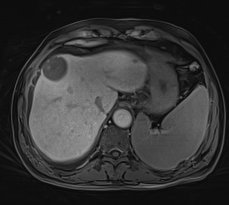

生命感知自由体部成像平台

MAGNETOM Vida磁共振系统可实现全新的生命感知自由体部成像:体部扫描时患者无需佩戴任何呼吸门控装置,全程自由呼吸就可完成扫描;在扫描过程中,Vida能根据病人的呼吸情况,实时控制磁共振信号采集;在BioMatrix生命矩阵系统的协助下,Vida可实现业界最快的动态增强成像——自由动态增强扫描,即:没有传统的增强期相,而是可以重建出指定的任意时间点的增强图像。

生命感知的自由动态增强

自由呼吸完成扫描,可冻结各个期相肝脏与腹壁运动